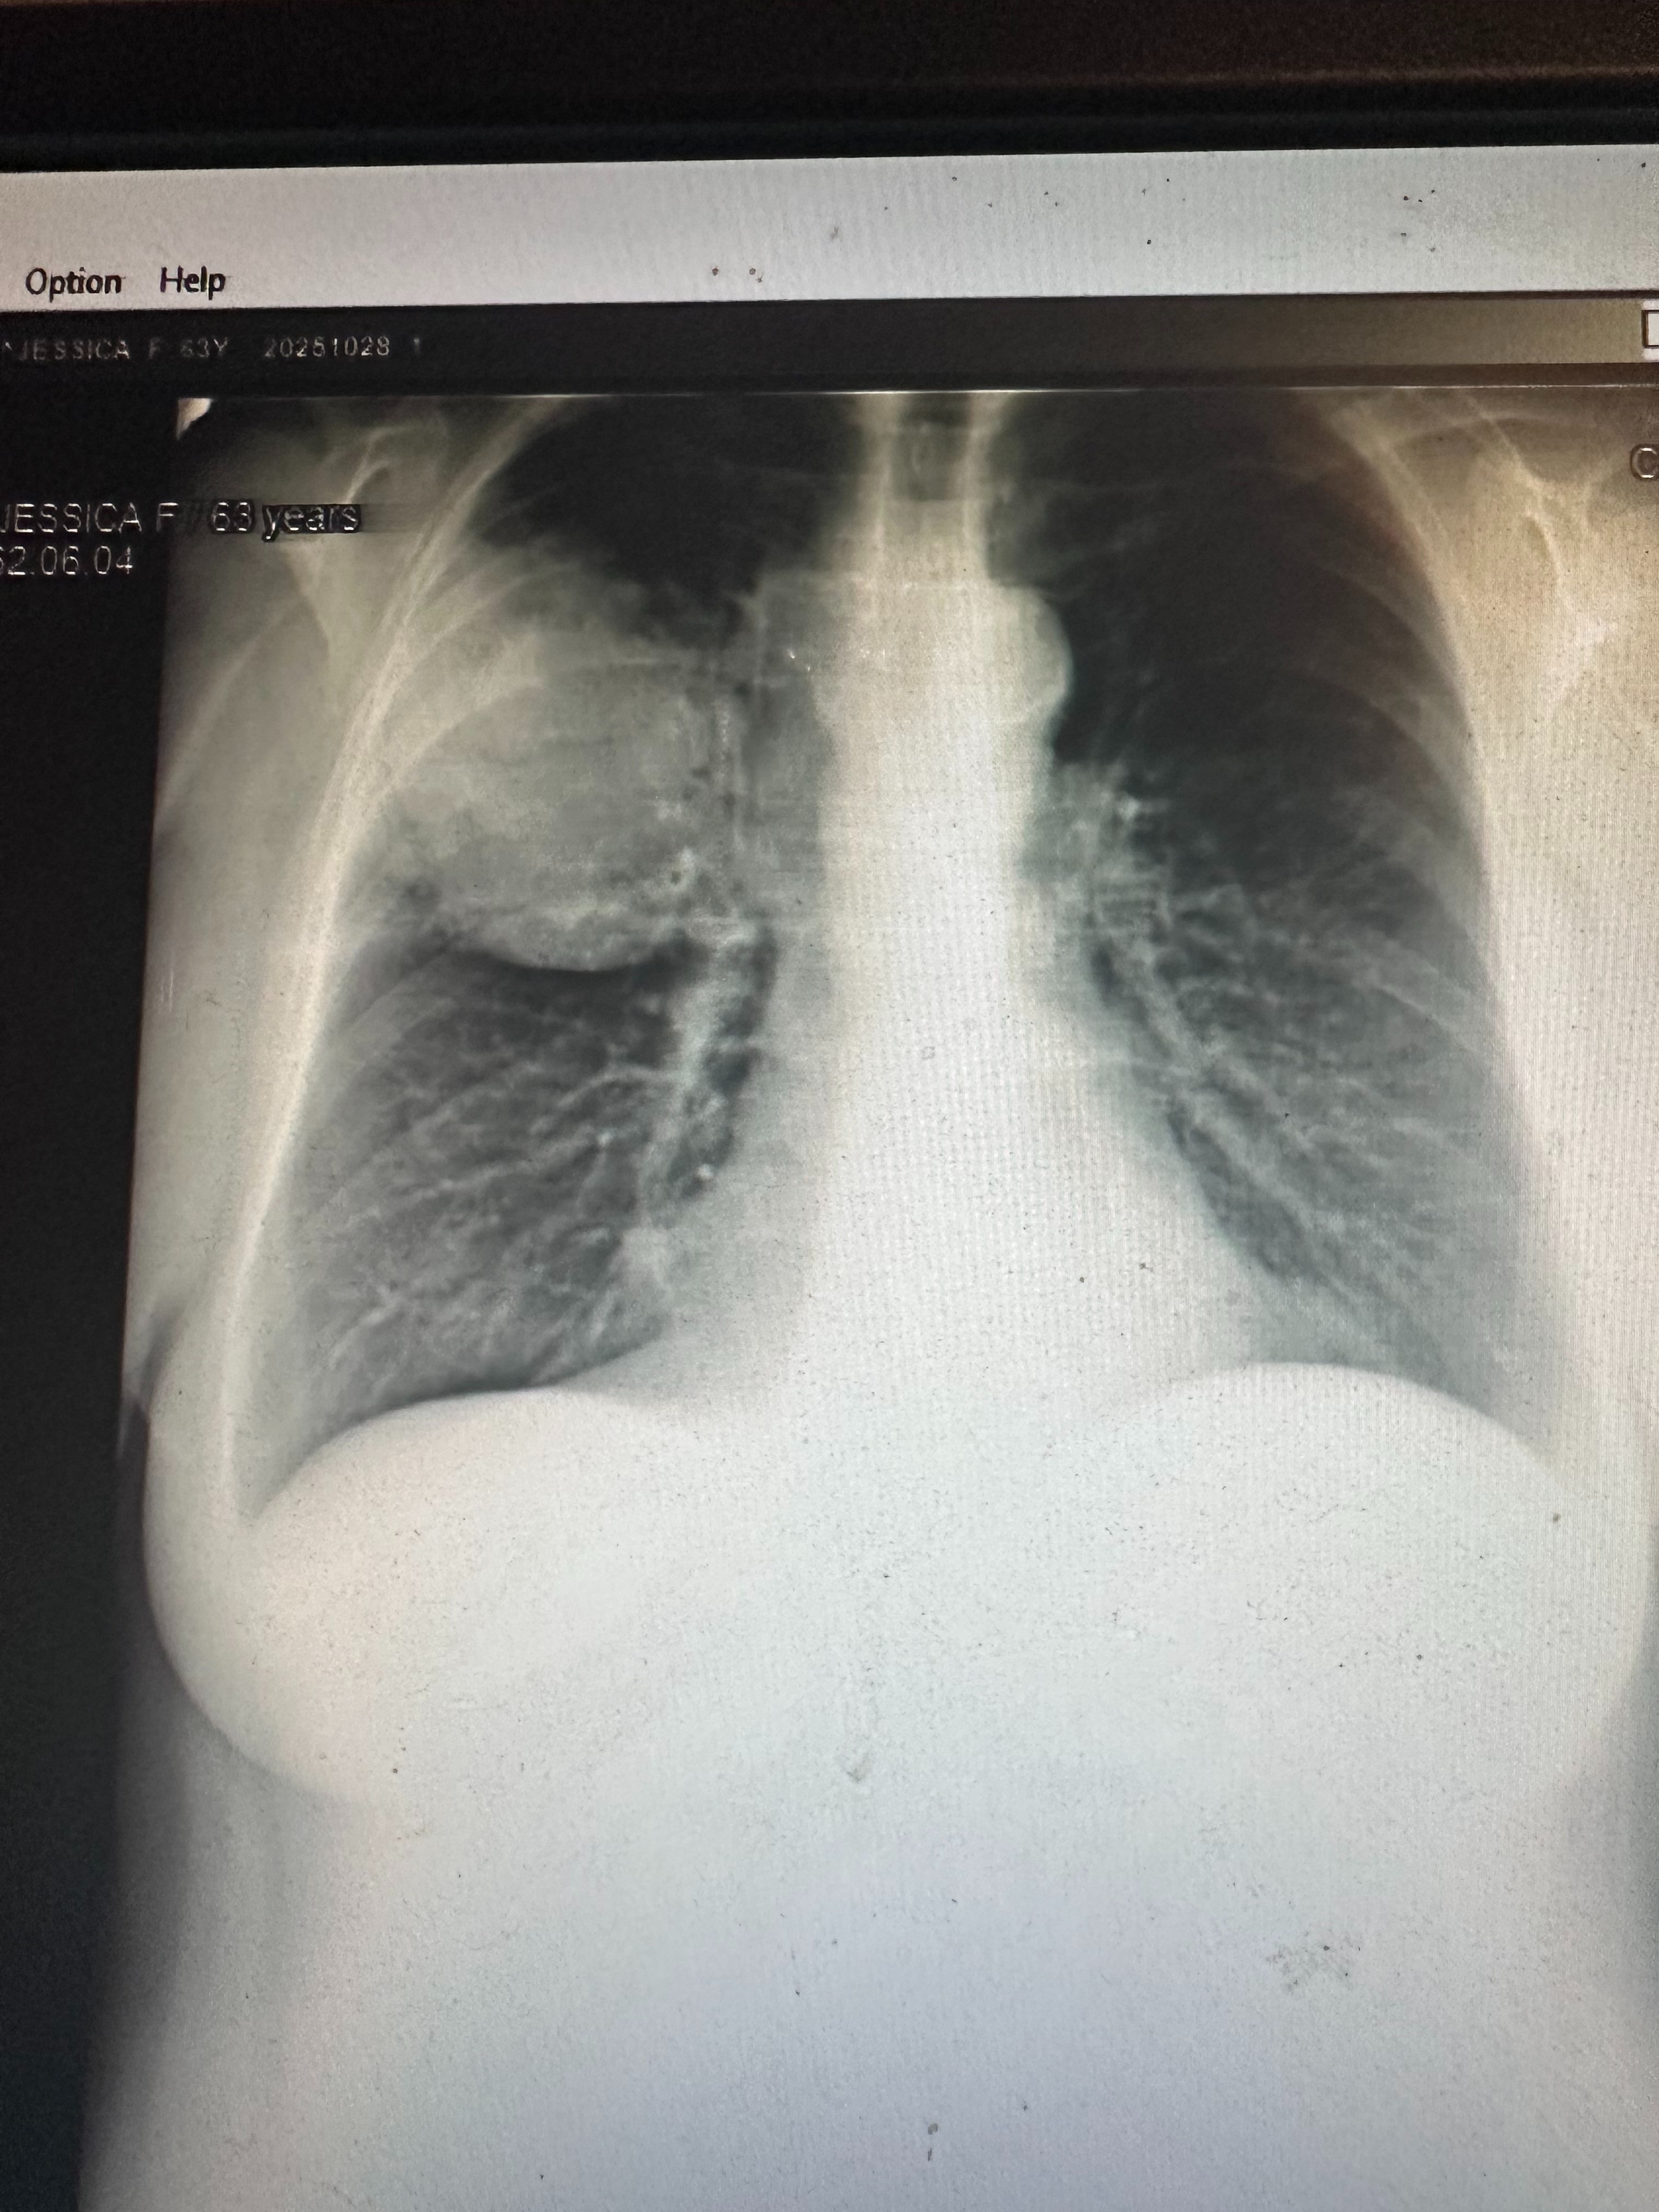

In early October, she lost her father on October 1st, and was still grieving that loss when, later that same month, our world was turned upside down again. In late October, she was diagnosed with stage 4 lung cancer. We’re still waiting for more test results and treatment options, but that day changed everything. I’ll never forget the family meeting when my parents told us — how my dad held her hand at the table, both of them trying to stay strong for us even as the room went silent with shock and heartbreak.